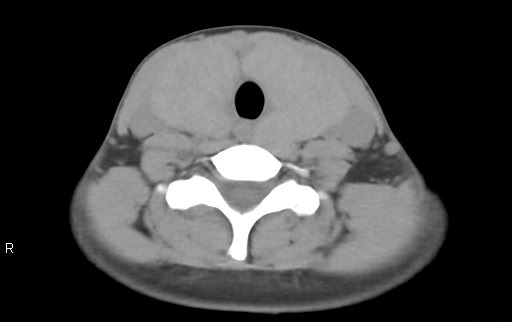

検査前は心拍数が120bpmを超えて、意思疎通困難・呼吸停止不可という患者の条件が非常に悪い中での撮影。最適心位相にて自動的に再構成された画像においてもブレが大きく、静止画像は全く期待できないと感じましたが、SnapShot Freeze2.0にて処理を行った画像はブレが大きく改善され大変きれいな画像であり、苦労することなく画像解析をすることが出来ました。

RevolusionCT_Sapporotokusyuukai_03.png